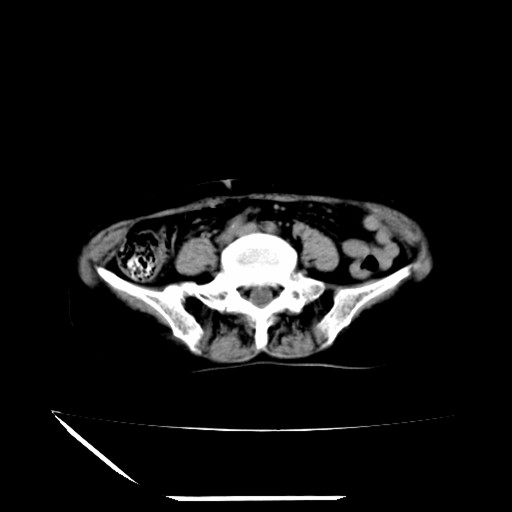

标题: CT16840:女-63岁,下腹部疼痛,

补充资料:血象是13.5,临床拟诊阑尾炎

本人诊断是右肾周围炎,阑尾炎,盆腔少许积液!

诊断右肾周围炎是因为我图像没有发完,诊断阑尾炎是因为相当于阑尾区连续两个层面可以看到增粗的阑尾显影。

支持阑尾炎!局部腹膜增厚,脂肪密度增高。应该手术治疗。